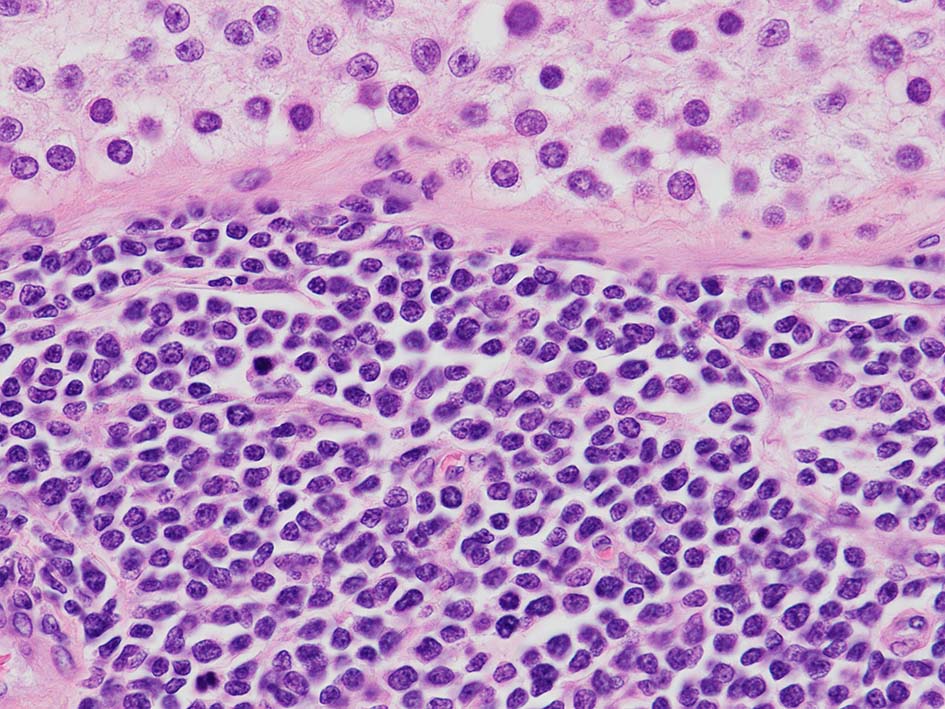

loupe像Aの領域: 精細管をスペアするように, 小型リンパ球優位, 一部中型のlymphoid cellsがシート状密に浸潤増殖する. tubulesのほとんどにはlymphoid cellsが浸潤していないが, LELに似たようなlympho-tubular lesionが少数認められた. x400高倍率では, 増殖細胞は, 粗く, 凝集したクロマチンをもつ類円形, non-cleavedな核をもつ細胞質の乏しいlymphoid cellsである. 核小体か凝集したクロマチンかわかりにくい.

白膜には密に腫瘍性リンパ球が浸潤増殖し, 肥厚, 一部は上図loupe像のように, 腫瘤を形成している. 浸潤リンパ球は精巣実質内よりも, やや大きく, 多稜形, くびれのある核をもち, クロマチンは淡明で核小体が明瞭になってきている.

T-ALLでは, T-LBLでは、一般にリンパ節の構築物が完全に消失し、被膜に浸潤していることが確認されます。 副皮質に部分的に病変が生じ、胚中心が温存されることもあります。時に、線維性骨格の伸展により、濾胞性リンパ腫に類似した多結節性パターンが生じることがある。 T-LBLでは核小体や細胞質はあまり目立たないが、星空効果が見られ、バーキットリンパ腫を模倣することがある。 芽球の核は丸いものと畳み込まれたものがある。有糸分裂図形はしばしば多数存在する。 胸腺では、胸腺実質の広範な置換と周囲の線維脂肪組織への浸透性浸潤が見られる。